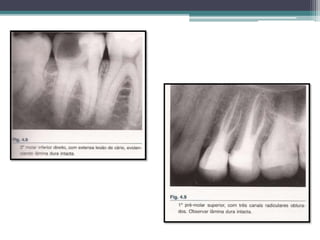

• RADIOGRAFICAMENTE: ligeiro aumento do espaço

periodontal apical, mas nem sempre pode ser detectado;

• Sugestão de sinal radiográfico de aumento do espaço

periodontal apical não é um sinal patognomônico dessa

alteração;